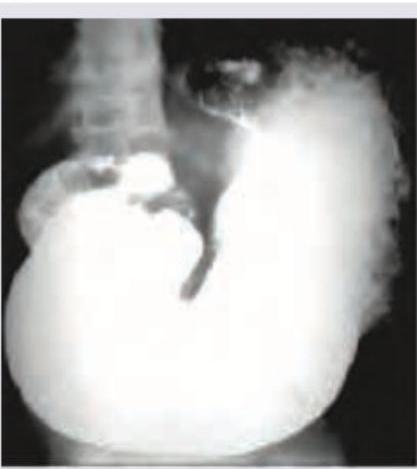

The following barium meal shows:

Explanation: ***Gastric outlet obstruction*** - The barium meal shows a **markedly distended stomach** with a large amount of retained contrast material filling the stomach, indicating impaired emptying. - There is minimal or no passage of barium into the duodenum, characteristic of a **physical barrier** preventing gastric emptying. *Normal study* - A normal barium meal would show the contrast passing readily from the stomach into the **duodenum and small bowel** within a short period. - The stomach size and emptying rate would be within typical physiological limits, unlike the distension seen here. *Esophageal varices* - Esophageal varices would appear as **irregular, serpiginous filling defects** within the esophagus, which is not the primary finding in this image. - The major abnormality seen is related to gastric emptying, not esophageal morphology. *Gastric antral vascular ectasia* - Gastric antral vascular ectasia (water-melon stomach) typically appears as **longitudinal red streaks or spots** in the antrum on endoscopy. - It would not manifest as severe gastric distention and obstruction to outflow on a barium meal; radiological findings are often subtle or related to mucosal abnormalities.